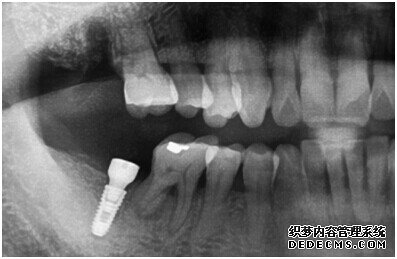

牙齿拍片初步检查

刘女士牙齿拍片初步检查

专家诊断:最后一颗牙齿通常不易清洁,且牙齿长了蛀牙之后也不容易发现,很多人就跟 刘女士一样发现的时候就已经是蛀牙中期甚至是后期了,这个时候一定要尽早治疗。不然和刘女士一样必须拔牙是非常可惜的。

由CT片检查来看,刘女士口腔健康环境还是很好的,牙槽骨也适合种植牙的条件,而且由我们最后一颗牙是非常重要的,经过专家的建议和详细解释了原因之后,刘女士选择了美国百康种植牙。